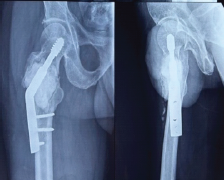

Giant Cell Tumor of the Proximal Femur with Pathological Fracture of Femoral neck

Gagandeep Gupta , Abhishek Singh , Shivang Kala , Akhilesh Saini , Shristi Singh , Sopan Shende

………………………………p.113-118